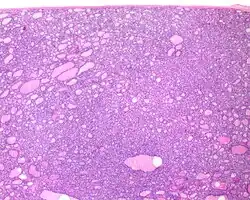

1) Encapsulated or partially encapsulated. The tumors are usually very well delimited or circumscribed, with the majority encapsulated, surrounded by a well formed fibrous connective tissue capsule.

2) Complete absence of invasion of any kind in a tumor that has been thoroughly and carefully evaluated with the whole capsule of the lesion sampled.

3) Predominantly follicular pattern of growth. Papillary structures should not be present. Further, solid, insular, or trabecular architecture must be <30% of the overall tumor for this category to still apply. Colloid (the material that thyroid follicular cells create) is easily identified throughout.